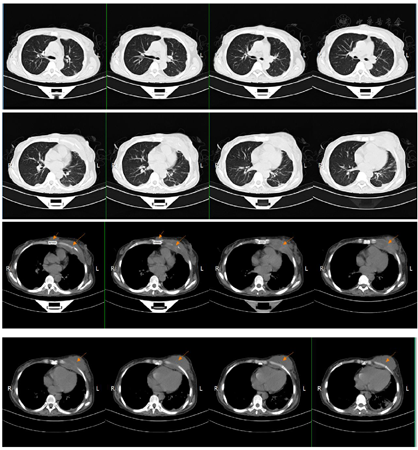

2018年7月2日患者第二次我院住院诊治,此时患者仍有发热,伴额头、左颈部,胸壁多处等多部位脓肿形成,胸部CT、颈部CT、头颅MR、腹部MR较前均有进展,多部位脓肿形成(图1,图2,图3,图4),入院后予B超引导下胸壁脓肿穿刺引流(图5),穿出脓液60 ml左右,穿刺液涂片抗酸阳性,穿刺液培养提示:非结核分枝杆菌生长,菌种鉴定提示疑似胞内分枝杆菌,患者既往血培养鉴定提升哥伦比亚分枝杆菌,考虑患者为播散性哥伦比亚分枝杆菌病,根据MIC结果予调整方案为AmRClrMfxE抗分枝杆菌治疗,后因耳鸣停Am,因药物热不能排除停用R,后调整方案为ClrMfxELzd+替加环素抗分枝杆菌感染,地塞米松减轻炎性反应,治疗后患者体温恢复正常,予出院回当地继续ClrMfxELzd+多西环素抗分枝杆菌治疗。

哥伦比亚分枝杆菌感染临床表现一般无特异性,一般以感染最常见感染部位为肺部,此外还发生于淋巴结、骨、皮肤、胃肠道等部位[2]。哥伦比亚分枝杆菌病肺部受累的影像学表现报道也较少,多无特异性,胸部CT可表现多种征象,如结节、实变、支气管扩张、磨玻璃密度影、纤维索条影、多发空洞、纵隔淋巴结肿大等[3,4]。哥伦比亚分枝杆菌病淋巴结病变表现为淋巴结肿大,CT增强扫描可表现为环状强化[5],骨关节受累可表现为多发溶骨性骨质破坏[6],本例表现播散性感染,肺部表现为双肺粟粒样改变,伴结节条索影,治疗后期出现两侧胸腔积液,纵隔多发淋巴结增大,环形强化不明显。本病例以骨骼侵犯起病,颅骨、颈椎、胸椎、腰椎、肋骨、髋关节,股骨均发生破坏,以侵蚀性溶骨改变为主,伴骨破坏处脓肿形成。